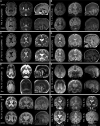

Vacuolar-type H+-ATPase (V-ATPase) is a multimeric complex present in a variety of cellular membranes that acts as an ATP-dependent proton pump and plays a key role in pH homeostasis and intracellular signalling pathways. In humans, 22 autosomal genes encode for a redundant set of subunits allowing the composition of diverse V-ATPase complexes with specific properties and expression. Sixteen subunits have been linked to human disease. Here we describe 26 patients harbouring 20 distinct pathogenic de novo missense ATP6V1A variants, mainly clustering within the ATP synthase α/β family-nucleotide-binding domain. At a mean age of 7 years (extremes: 6 weeks, youngest deceased patient to 22 years, oldest patient) clinical pictures included early lethal encephalopathies with rapidly progressive massive brain atrophy, severe developmental epileptic encephalopathies and static intellectual disability with epilepsy. The first clinical manifestation was early hypotonia, in 70%; 81% developed epilepsy, manifested as developmental epileptic encephalopathies in 58% of the cohort and with infantile spasms in 62%; 63% of developmental epileptic encephalopathies failed to achieve any developmental, communicative or motor skills. Less severe outcomes were observed in 23% of patients who, at a mean age of 10 years and 6 months, exhibited moderate intellectual disability, with independent walking and variable epilepsy. None of the patients developed communicative language. Microcephaly (38%) and amelogenesis imperfecta/enamel dysplasia (42%) were additional clinical features. Brain MRI demonstrated hypomyelination and generalized atrophy in 68%. Atrophy was progressive in all eight individuals undergoing repeated MRIs. Fibroblasts of two patients with developmental epileptic encephalopathies showed decreased LAMP1 expression, Lysotracker staining and increased organelle pH, consistent with lysosomal impairment and loss of V-ATPase function. Fibroblasts of two patients with milder disease, exhibited a different phenotype with increased Lysotracker staining, decreased organelle pH and no significant modification in LAMP1 expression. Quantification of substrates for lysosomal enzymes in cellular extracts from four patients revealed discrete accumulation. Transmission electron microscopy of fibroblasts of four patients with variable severity and of induced pluripotent stem cell-derived neurons from two patients with developmental epileptic encephalopathies showed electron-dense inclusions, lipid droplets, osmiophilic material and lamellated membrane structures resembling phospholipids. Quantitative assessment in induced pluripotent stem cell-derived neurons identified significantly smaller lysosomes. ATP6V1A-related encephalopathy represents a new paradigm among lysosomal disorders. It results from a dysfunctional endo-lysosomal membrane protein causing altered pH homeostasis. Its pathophysiology implies intracellular accumulation of substrates whose composition remains unclear, and a combination of developmental brain abnormalities and neurodegenerative changes established during prenatal and early postanal development, whose severity is variably determined by specific pathogenic variants.